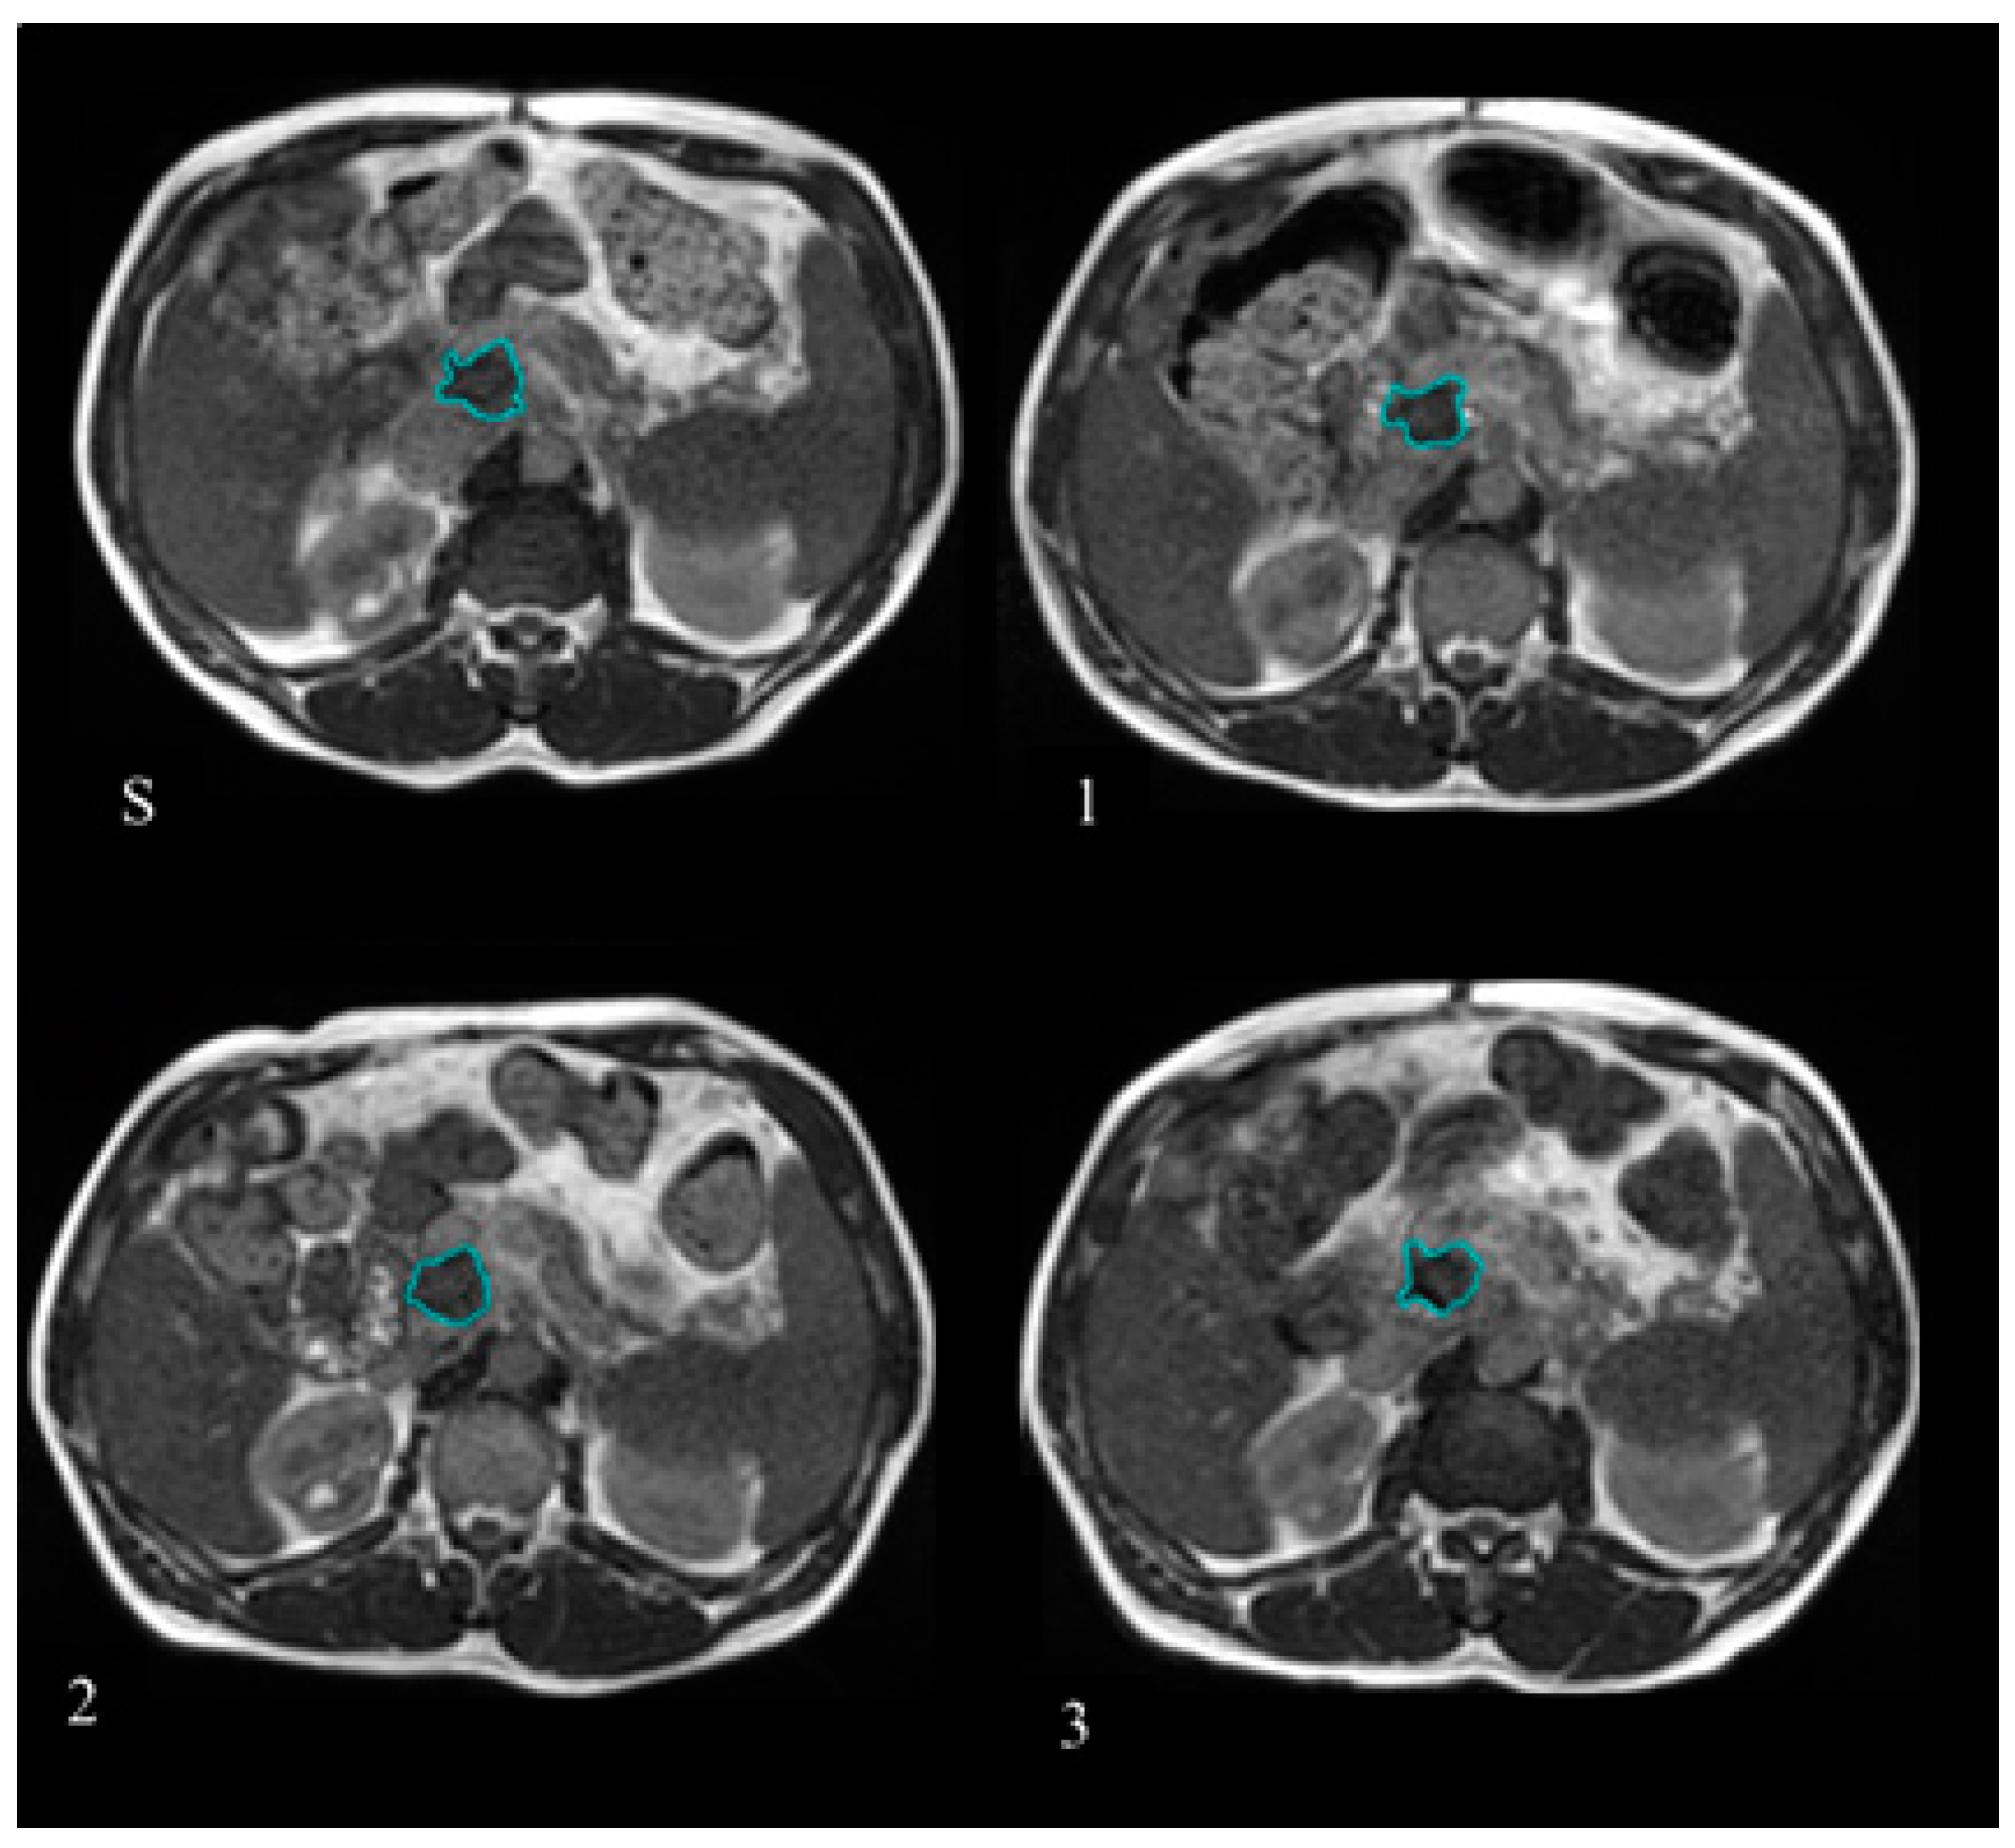

GTV delineation was retrospectively checked for anatomical consistency on the MR images selected for the analysis using the MIM software (version 6.7.6 MIM Software Inc., Cleveland, OH, USA) by two radiation oncologist experts in the gastrointestinal malignancies. Figure 1 reports the example of one patient where the GTV was delineated at simulation and at the treatment fractions selected to have BED levels of 20, 40, and 60 Gy.

Figure 1.

Gross tumour volume (GTV) delineated at the treatment simulation (S) and at the different treatment fractions selected for the Delta Radiomics analysis, corresponding to BED levels of 20 Gy (1), 40 Gy (2), and 60 Gy (3). The GTV contours are reported in blue lines